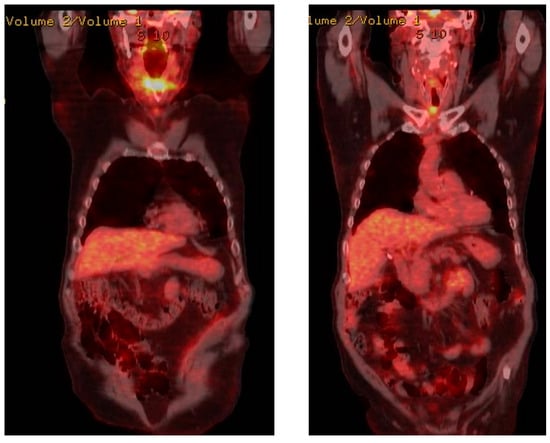

During the postoperative period, the patient received chemotherapy treatment. In that period, he also had a bone scintigraphy and an 18-F-FDG PET/CT. (Figure 7).

Figure 7. Postoperative 18-F-FDG PET/CT.